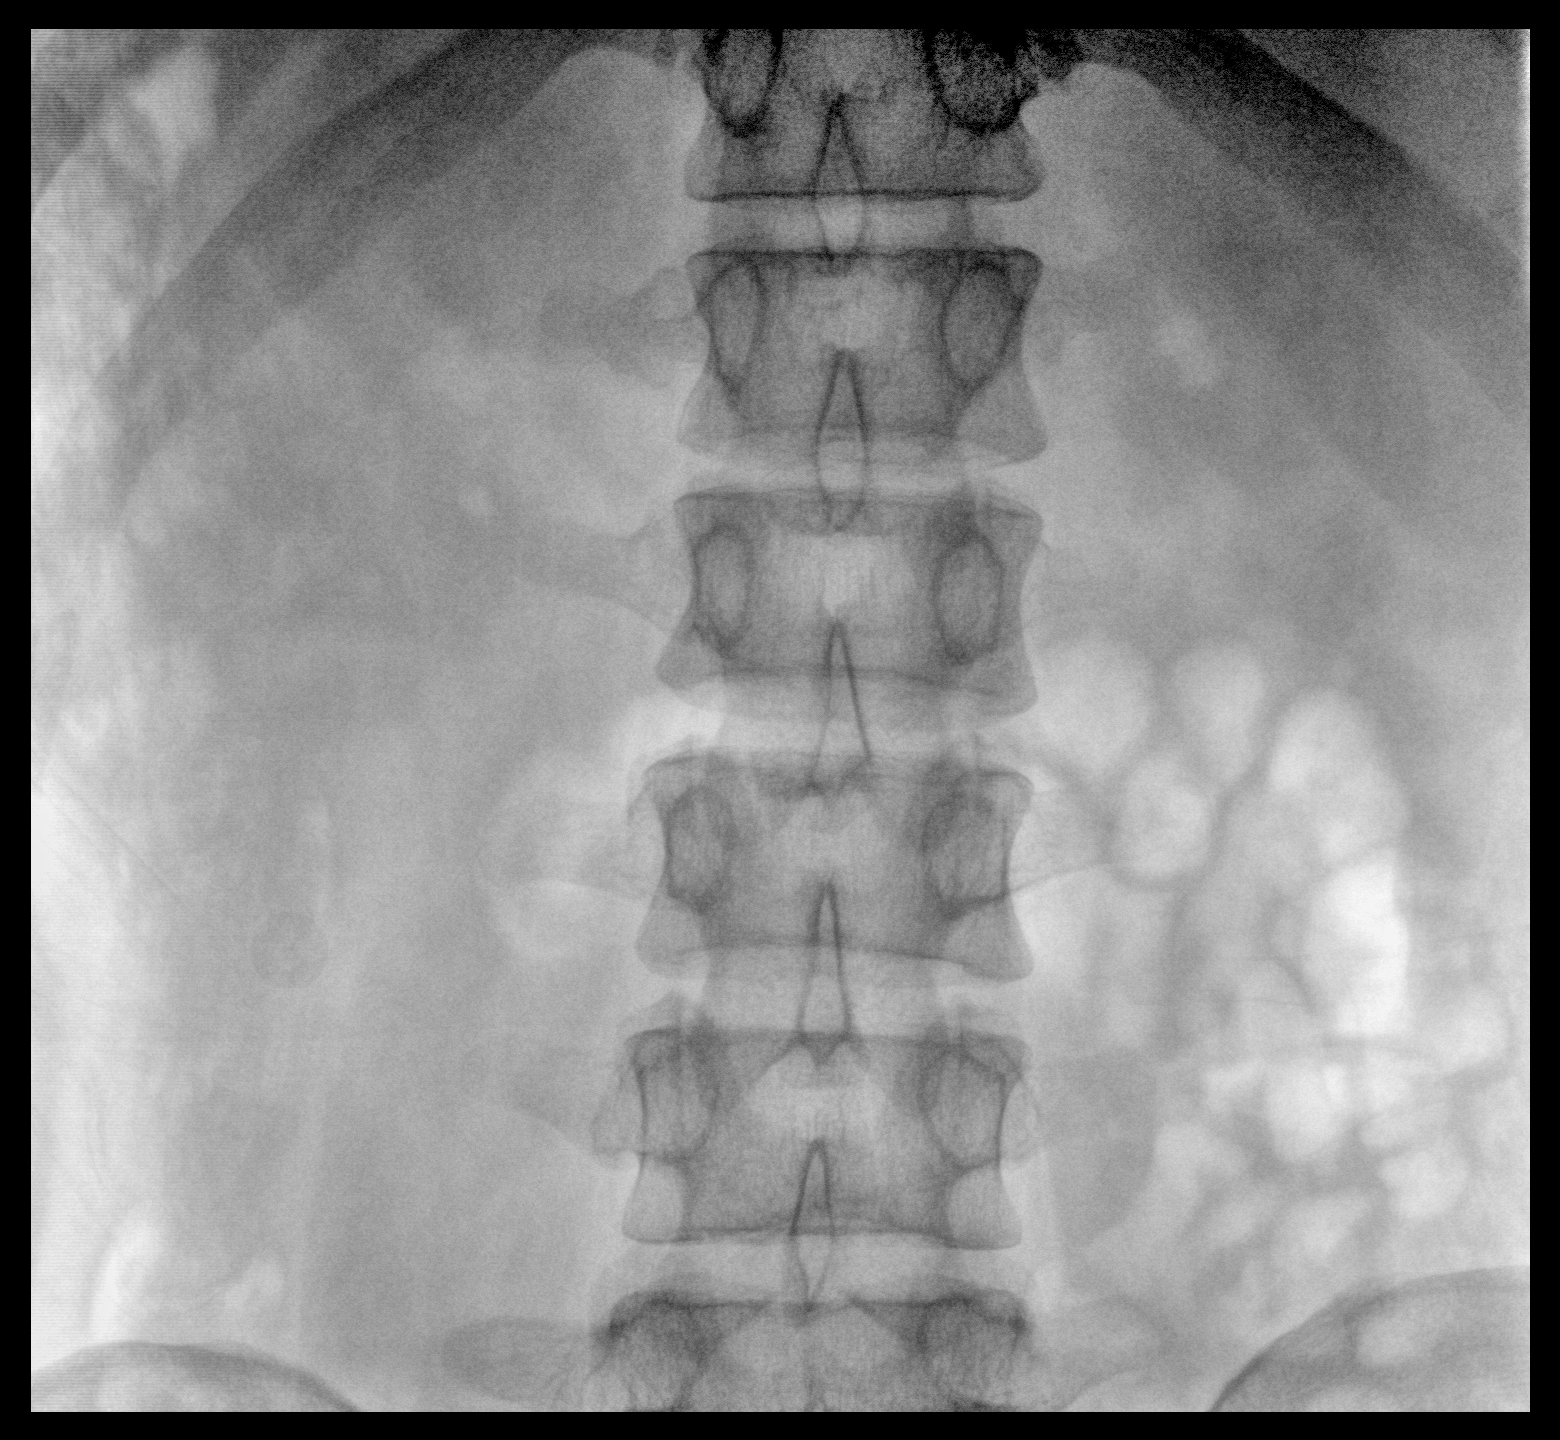

大尺寸動(dòng)態(tài)平板探測(cè)器,高DQE、低噪聲、圖像清晰。采用多分辨率圖像增強(qiáng)處理技術(shù),不同部位不同圖像處理算法,滿足客戶多樣化的需求。

采用智能變頻脈沖透視技術(shù),優(yōu)化圖像質(zhì)量的同時(shí)降低輻射劑量,呵護(hù)醫(yī)患健康